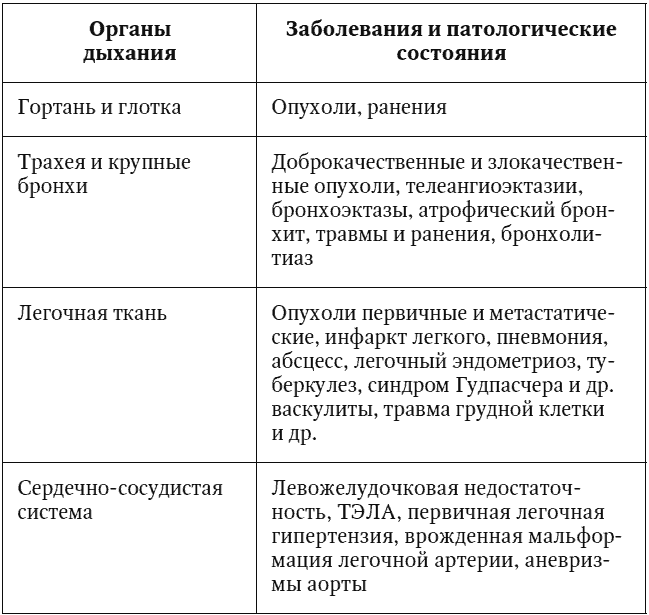

В целом заболевания и патологические состояния, которые потенциально могут осложниться развитием кровохарканья и легочного кровотечения, можно представить в виде таблицы (табл. 1).

Таблица 1

Заболевания и патологические состояния, которые потенциально могут осложниться развитием кровохарканья и легочного кровотечения